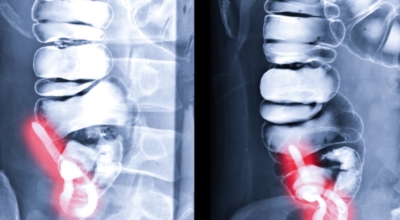

맹장염은 맹장 끝 충수돌기에 생기는 염증이라고 볼 수 있다고 하며, 보통 맹장염으로 알려져 있기는 1개 실질적으로는 부위가 충수돌기이기 때문에 의학 용어로는 충수염이라고 부르는 단어가 더욱더 정확하다고 해요. 맹장염(충수염)은 한국 사람들이 수술을 진행하는 질병 5위라고 불릴 정도로 수시로 발생하며 매해 약 10만 명 정도가 수술을 받을 만큼 통상적으로 생기는 질환이예요.

복통과 소화불량으로부터 시작하는 초기 맹장염 증상이 나타나는데 많은 분들이 소화기 계통 질환으로 오인해 약만 먹고 그냥 지나치는 경우가 많다고 해요. 대장이 시작되는 부위를 맹장이라고 하며 그 끝부분에 약 5~10cm 정도의 길이로 꼬리처럼 달린 구조물을 충수 또는 충수돌기라고 그렇지만, 통상적으로 말하는 맹장염은 이 충수가 막히거나 눌려서 염증이 발생해 통증이 생기게 되는데 심할 경우 터지는 경우가 나타나기도 해요.

맹장염의 정확한 까닭은 항상 명확하지는 않아요. 하지만 충수가 막히거나 감염되었을 때 나타나는 것으로 여겨집니다. 막힘은 다음등의 다양한 요인으로 인하여 생기게 될 수 있습니다.

배설물: 맹장에 배설물이 축적되면 막힘을 일으켜 염증을 일으킬 수 있답니다. 확대된 림프성 여포: 충수에는 면역 체계의 일부인 림프성 여포가 들어있어요. 이 모낭이 커지면 맹장을 막고 염증을 일으킬 수 있습니다. 찌꺼기: 때로는 삼킨 껌 조각이나 씨앗등의 순수하지 않은 물질이 맹장에 달라붙어 염증을 일으킬 수 있습니다. 종양: 드물게 충수돌기에서 종양이 발생해서 염증을 일으킬 수 있습니다.